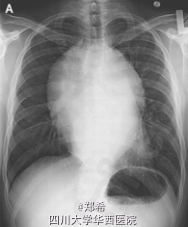

患者为30岁男性,2个月以来胸闷,气短,伴呼吸困难,吞咽困难,吞咽疼痛及体重下降14KG。3年前因I期精原细胞癌行睾丸切除术,术后失访。

心脏查体为窦性心率,并无杂音和奔马律,双肺听诊呼吸音清胸片以及CT发现后纵隔巨大包块。实验室检查发现人绒毛膜促性腺激素升高,为4miU/ml,正常<3。乳酸脱氢酶1400U/L(正常140-270)。甲胎蛋白正常。